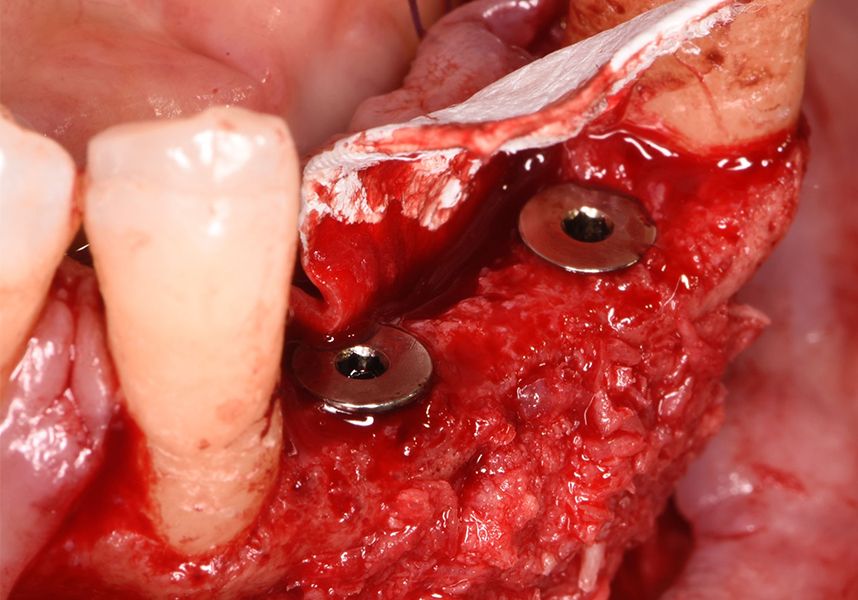

The patient was anesthetized and a flap was made from the distal area of tooth 43 up to 36. Then two Avinent Biomimetic Ocean IC implants of 3.5x10 were inserted in positions 32 and 42.

Respecting the three-dimensionally correct position of the implant led to bone fenestration, leaving the apical part of the apex of the implant exposed almost to the mid-point of its length at 42 and a third in 32.

To treat the defect, bone regeneration was carried out simultaneous to the surgical process, with an autologous bone graft from the patient. In the internal part of the graft we used autologous cortical bone obtained by scraping (Safescraper) and from the biological drilling, at low revolutions and without irrigation, from the other implant beds. In the external layer of the regeneration we used a xenograft (Genoss, Osteogenos) and this was covered with a reabsorbable collagen barrier membrane (Evolution STD, Osteogenos).